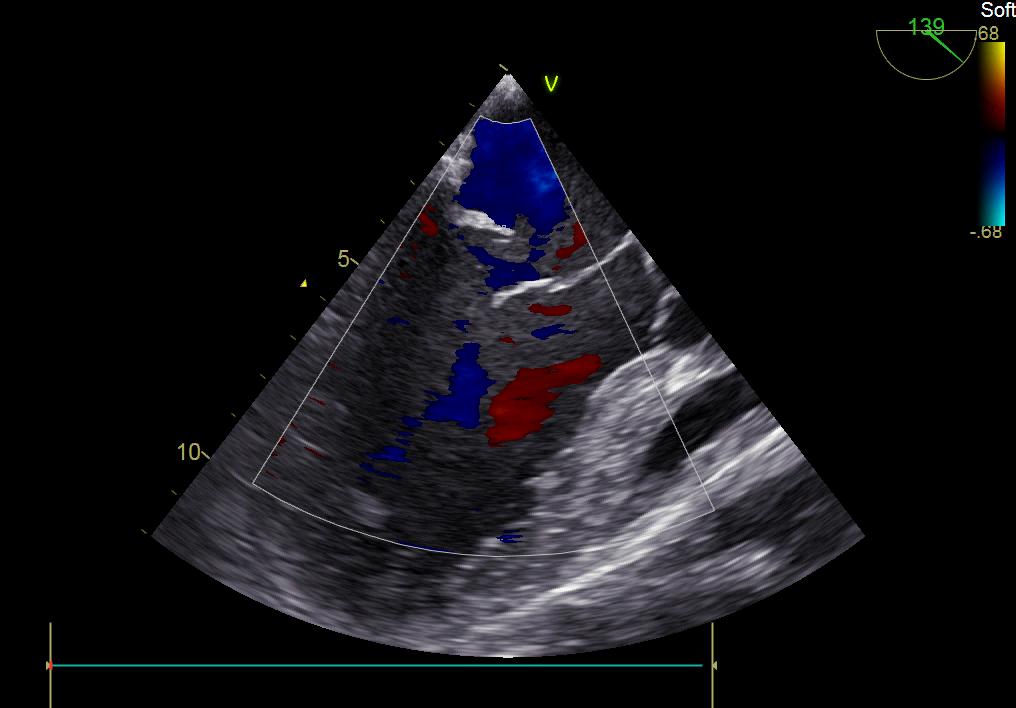

術前彩超